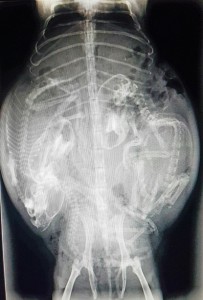

encore un caillou a la radio

Radiographie de face d’un chien ayant avalé un caillou